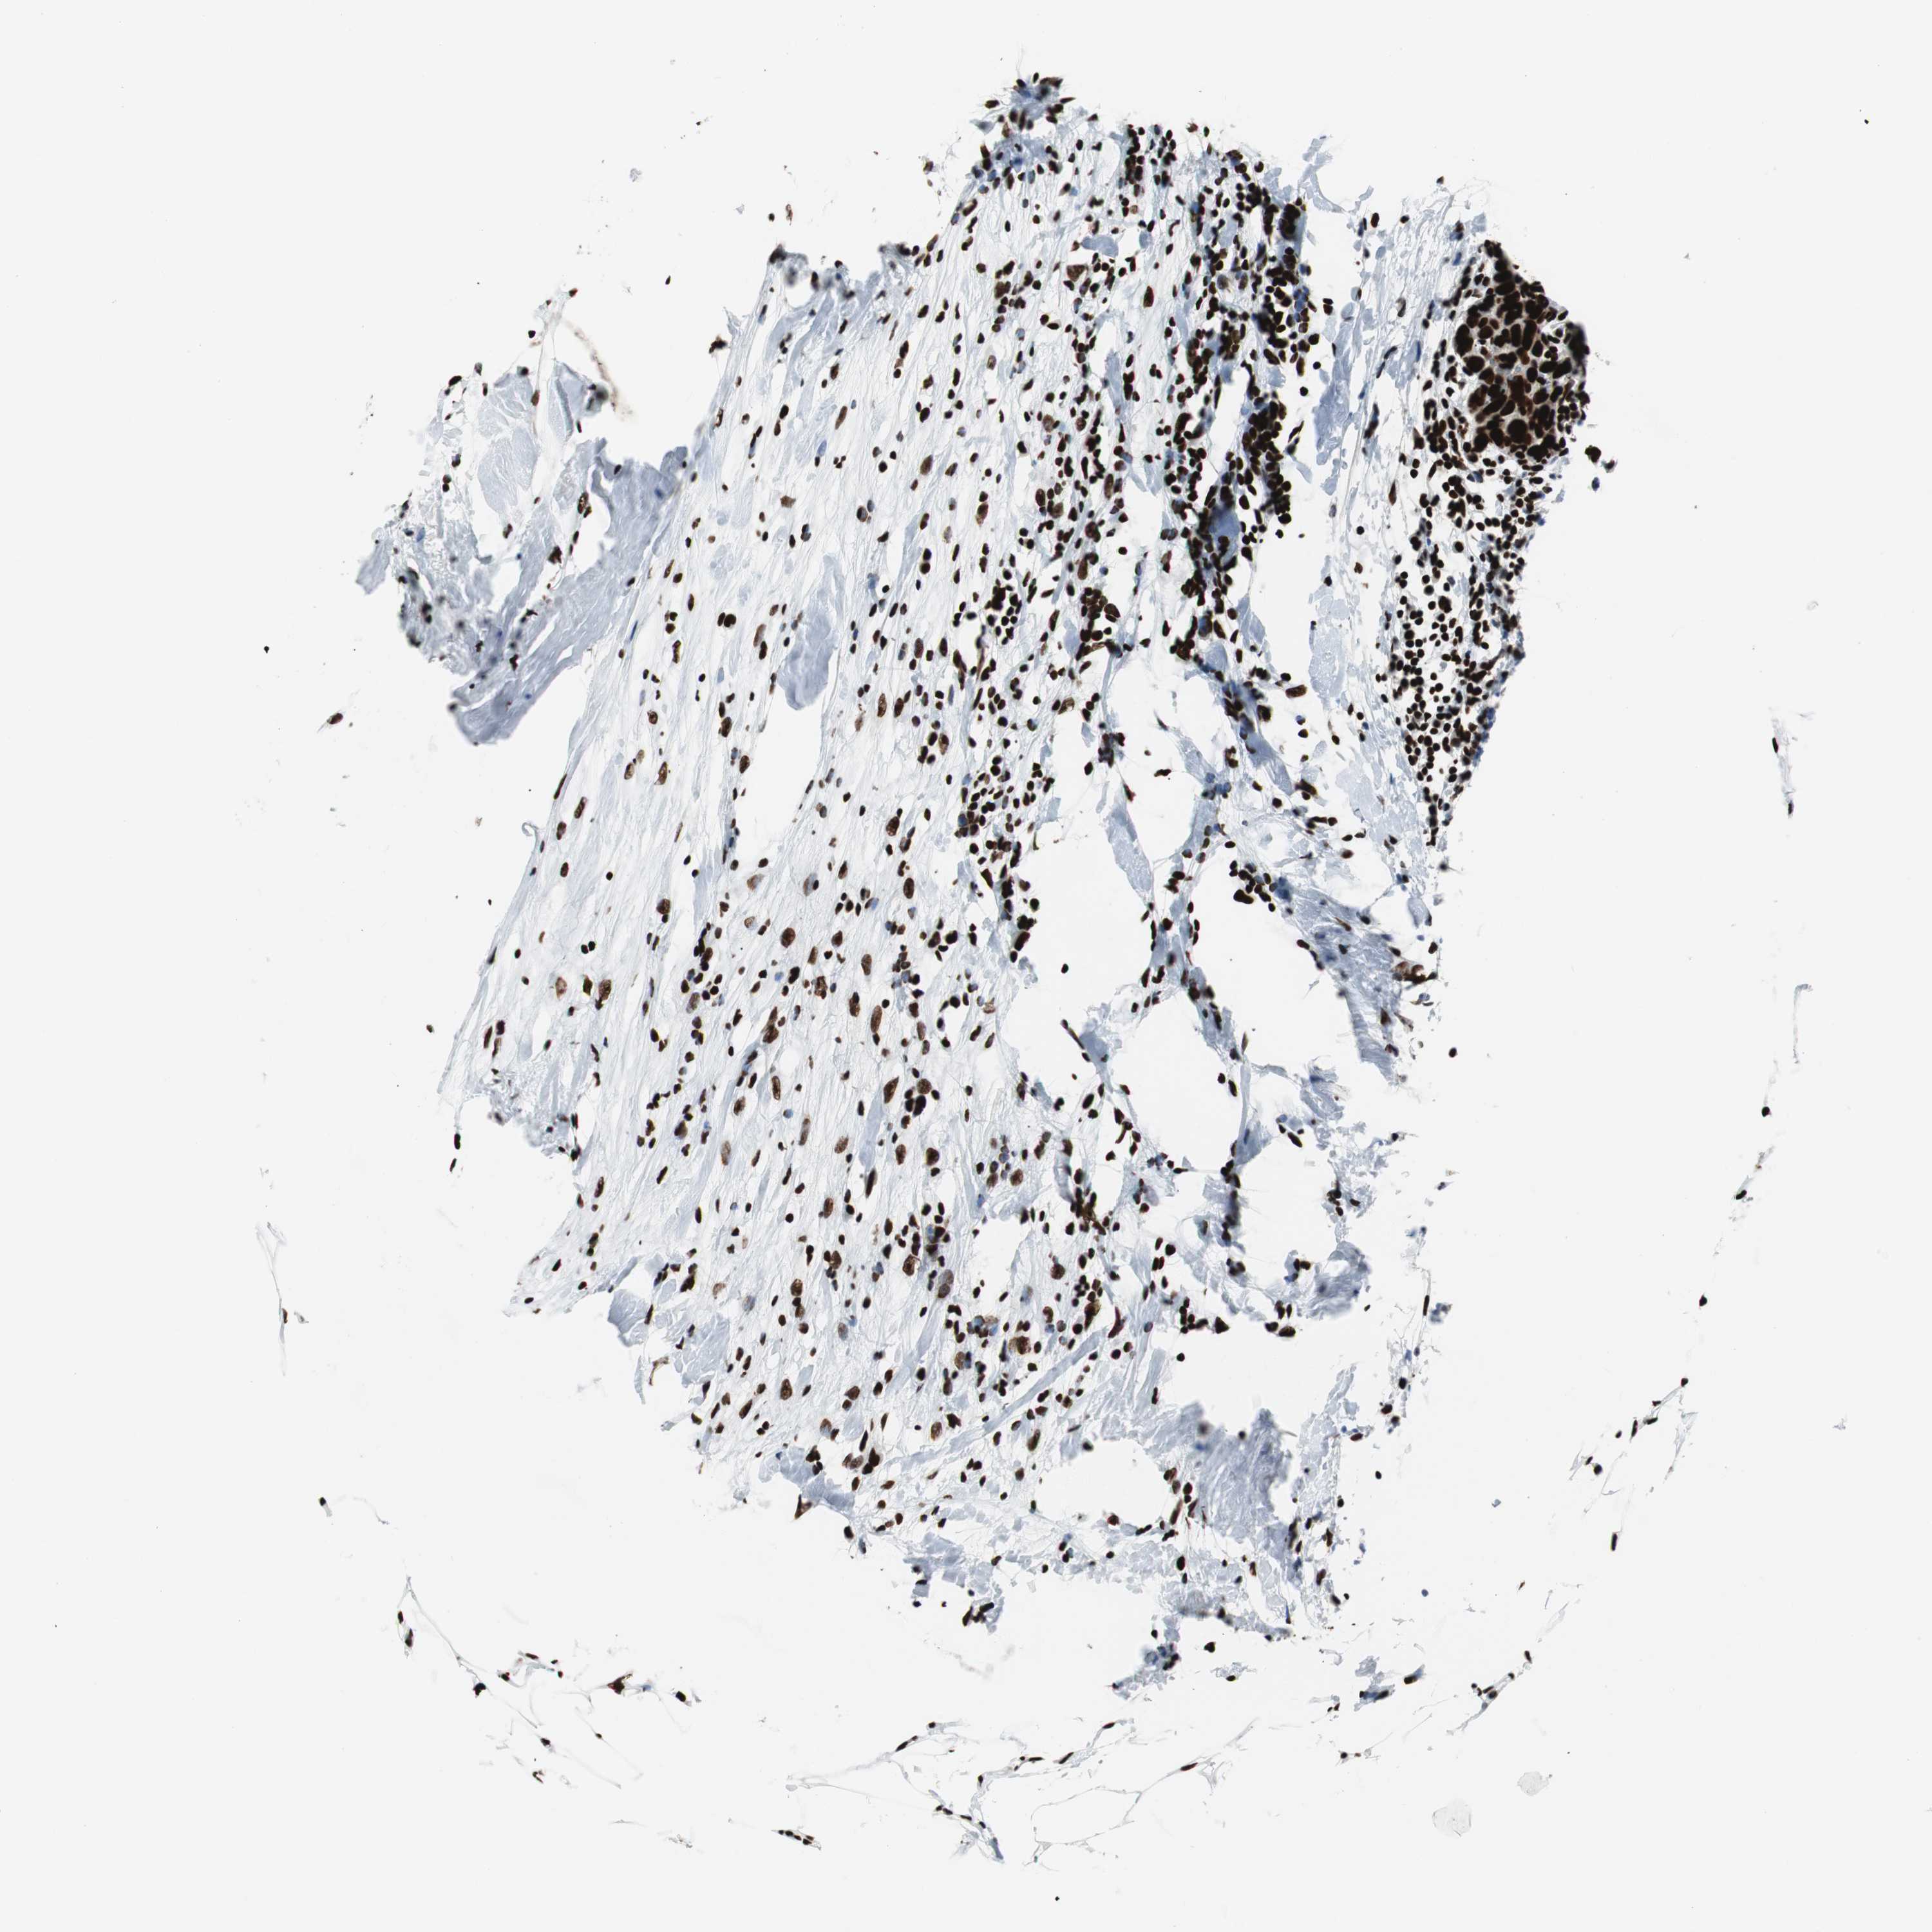

BRCA TCGA BRCA VALIDATION PROTEIN EXPRESSION